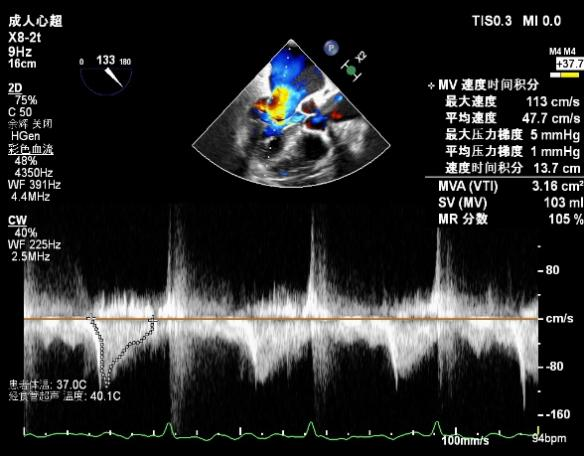

术前超声评估结果

术前超声诊断

3D-color MV view:源自于交界区的大量反流

肺静脉血流频谱逐渐恢复正向,后测量平均跨瓣压差:2mmHg

二尖瓣瓣口平均跨瓣压差:3mmHg